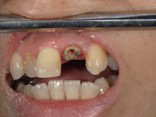

根っこ(歯根)が歯茎の中にあり、このままでは差し歯に出来ない状態です。